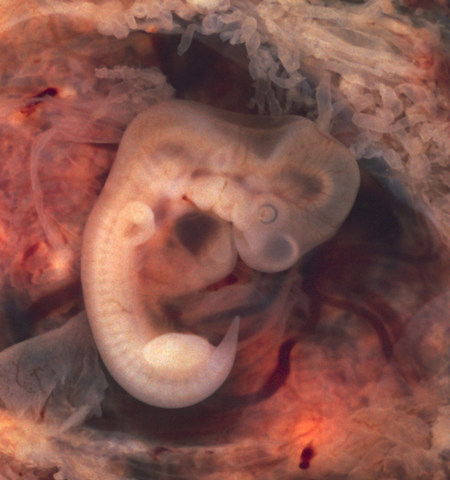

• PRIMER MES

PRIMER MES

es un embrión que consiste en dos capas de células, a partir de las cuales se desarrollarán todos sus órganos y las partes de su cuerpo.

• SEMANA 5

SEMANA 5

La quinta semana del embarazo ha comenzado, los pliegues celulares o gastrulación que mencionábamos en la cuarta semana del embarazo, empezarán en este segundo mes a tomar forma, órganos y tejidos se forman a partir de estos pliegues.

• SEXTA SEMANA

La sexta semana del embarazo se ha iniciado, el desarrollo de la región cefálica iniciada en la quinta semana del embarazo ha originado que ésta destaque notablemente comparándola con el resto del embrión, la cabeza se muestra encorvada y próxima al primitivo corazón

• SEPTIMA SEMANA

SEPTIMA SEMANA

Ya estás en la 7ª semana del embarazo, en el feto han comenzado a desarrollarse todos los órganos esenciales, los ojos continúan desplazándose hasta poder situarse en el frente de la cara y empiezan a formarse los párpados.

• OCTAVA SEMANA

OCTAVA SEMANA

Ya te encuentras en la 8ª semana del embarazo, en el feto ya se aprecia cómo se forman las orejas, los párpados, la nariz o el labio superior y se muestran con claridad.